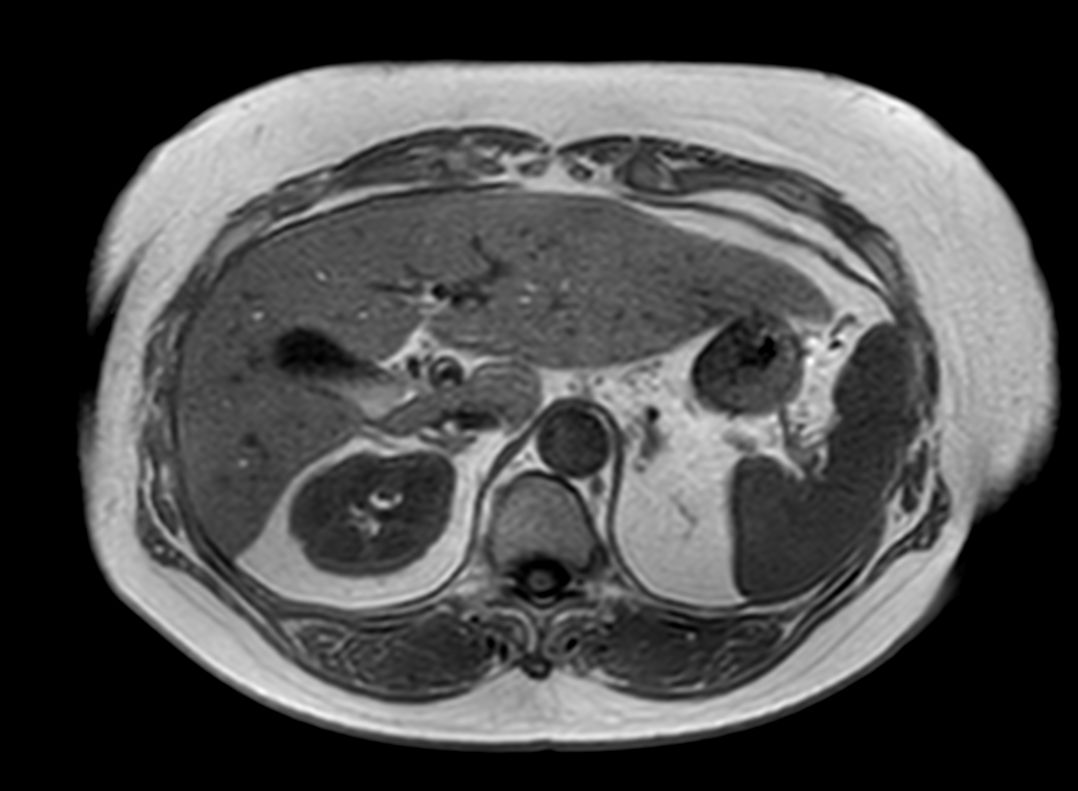

T2w TSE (single shot)

T1w FFE (In Phase)

T1w FFE (Out Phase)